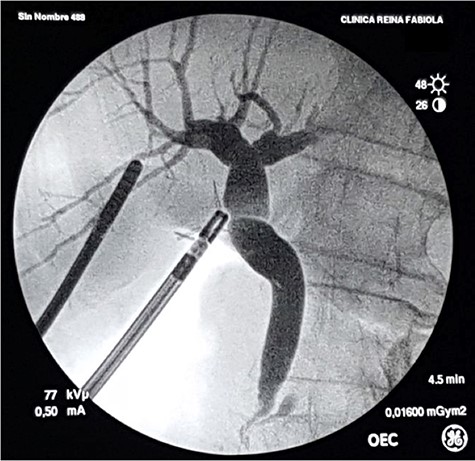

Control intraoperative cholangiography using a 5-Fr catheter and an Olsen clamp demonstrates free flow of contrast into the duodenum without defects or stenosis.